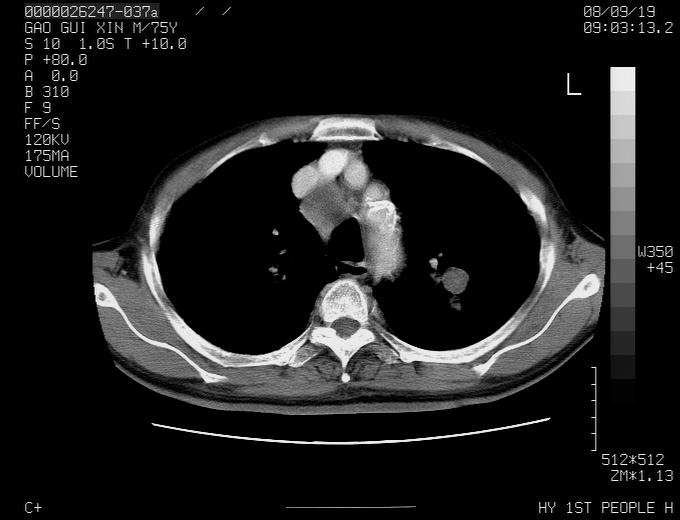

右上肺可见条索状影,并可见钙化,左上肺结节可以考虑为结核球,但气管前腔静脉后有肿大淋巴结,本人觉得左上肺结节不能排除转移瘤的可能,右上肺为陈旧性结核灶。

左肺上叶周围性肺癌并纵隔多组lnm.不可能是tb.

左肺上叶尖段瘢痕癌并纵隔淋巴结转移解释更好一些.

左肺周围癌并纵隔淋巴结转移,另一小结节是血管影

1)左肺上叶尖段周围型肺癌并纵隔淋巴结转移。2)冠状动脉及主动脉钙化。